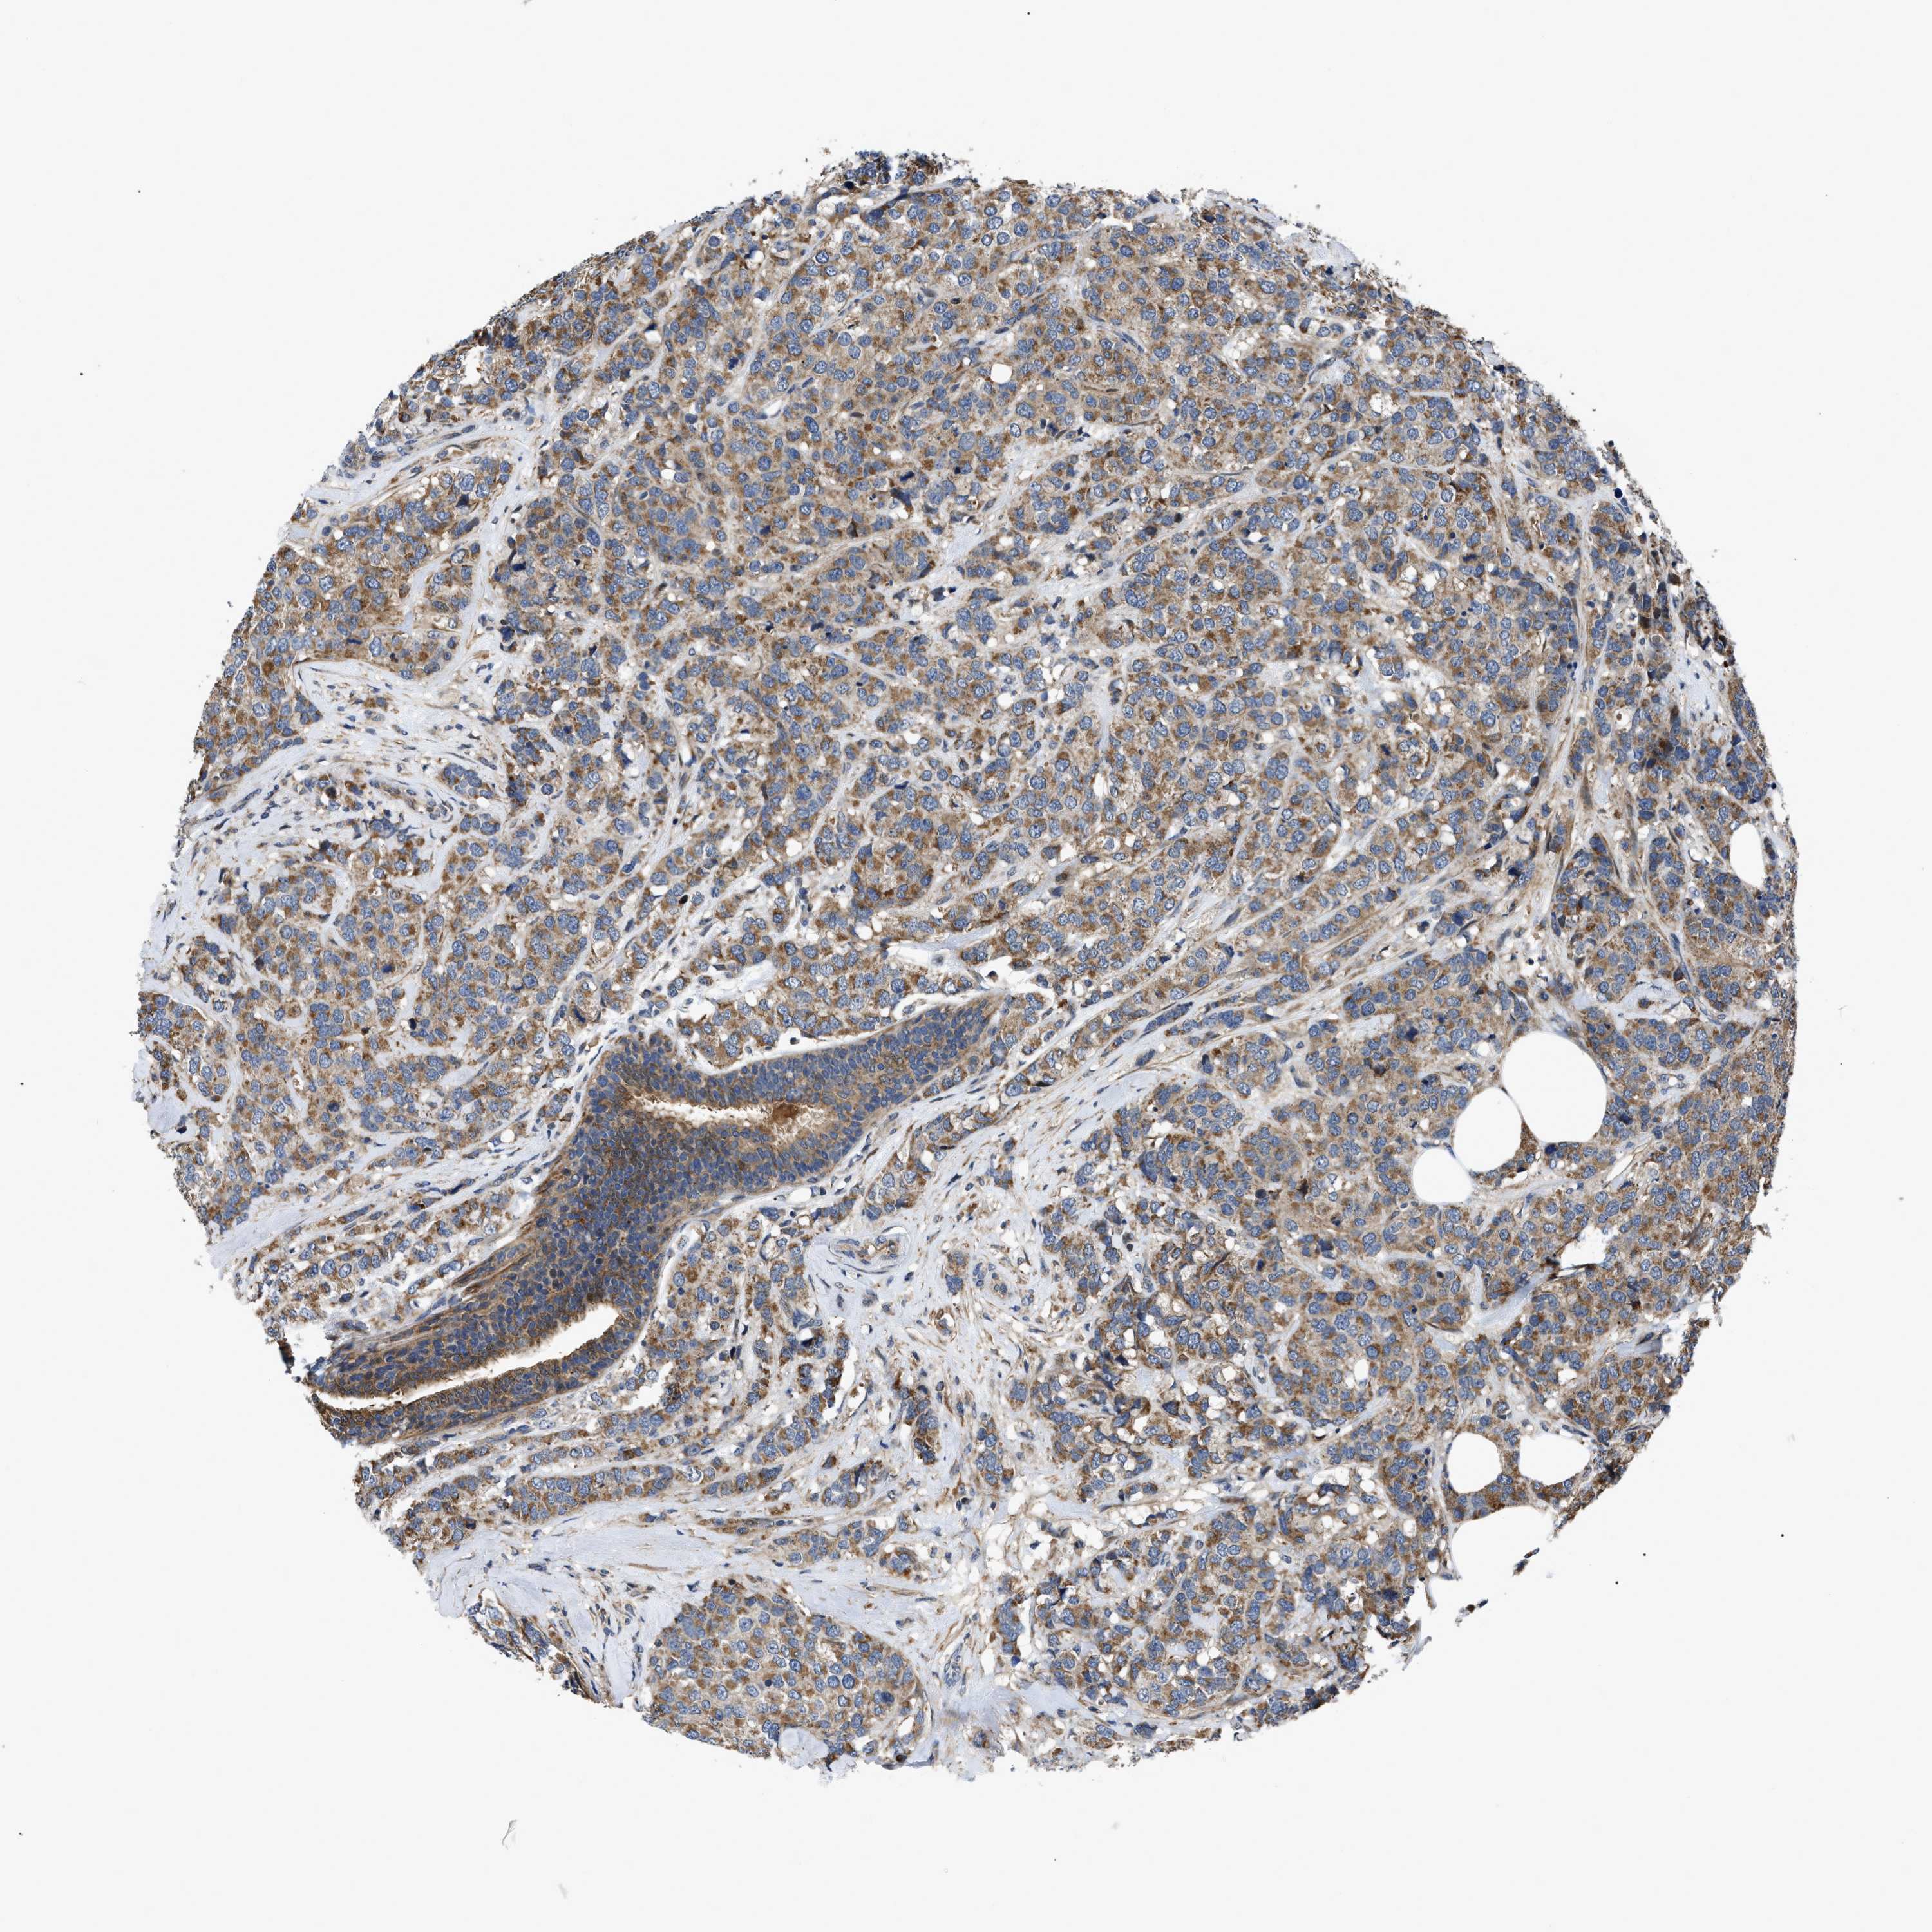

CANCER BREAST CANCER Show tissue menu

Breast cancer

Human cancer